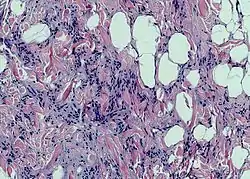

ورم شحمي مغزلي الخلايا[1] (بالإنجليزية: Spindle cell lipoma) هو ورم تحت جلدي عديم الأعراض بطيء النمو، ويَميل إلى إصابة ظهر ورقبة وأكتاف كبار السن من الرجال.[2]:625[3]